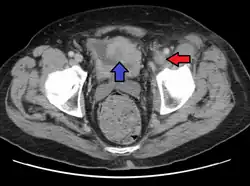

| A person with a two hour history of phlegmasia cerulea dolens (left leg, right side of image) |